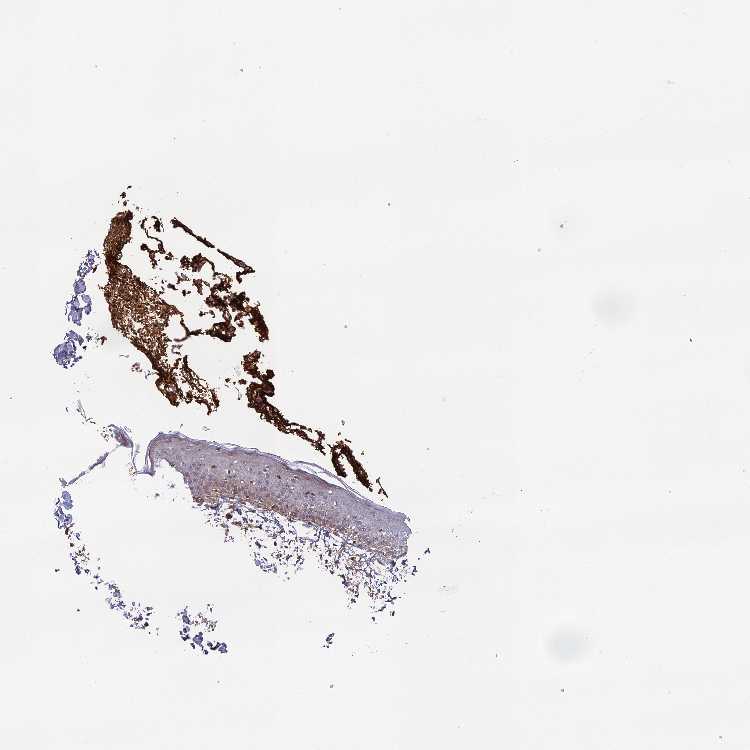

SKIN 2 - Antibody stainingi

Antibody staining in the annotated cell types in the current human tissue is reported as not detected, low, medium, or high, based on conventional immunohistochemistry profiling in selected tissues. This score is based on the combination of the staining intensity and fraction of stained cells.

Each image is clickable and will lead to virtual microscopy that enables deeper exploration of all samples and also displays staining intensity scores, fraction scores and subcellular localization as well as patient and tissue information for each sample.

Antibody HPA040959Antibody HPA043401

Cells in basal layer Medium-

Cells in corneal layer Not detected-

Cells in granular layer Medium-

Cells in spinous layer Medium-

Endothelial cells Medium-

Epidermal cells -Medium

Extracellular matrix Not detected-

Fibrohistiocytic cells High-

Langerhans cells Medium-

Lymphocytes High-

Melanocytes High-

Vascular mural cells Not detected-